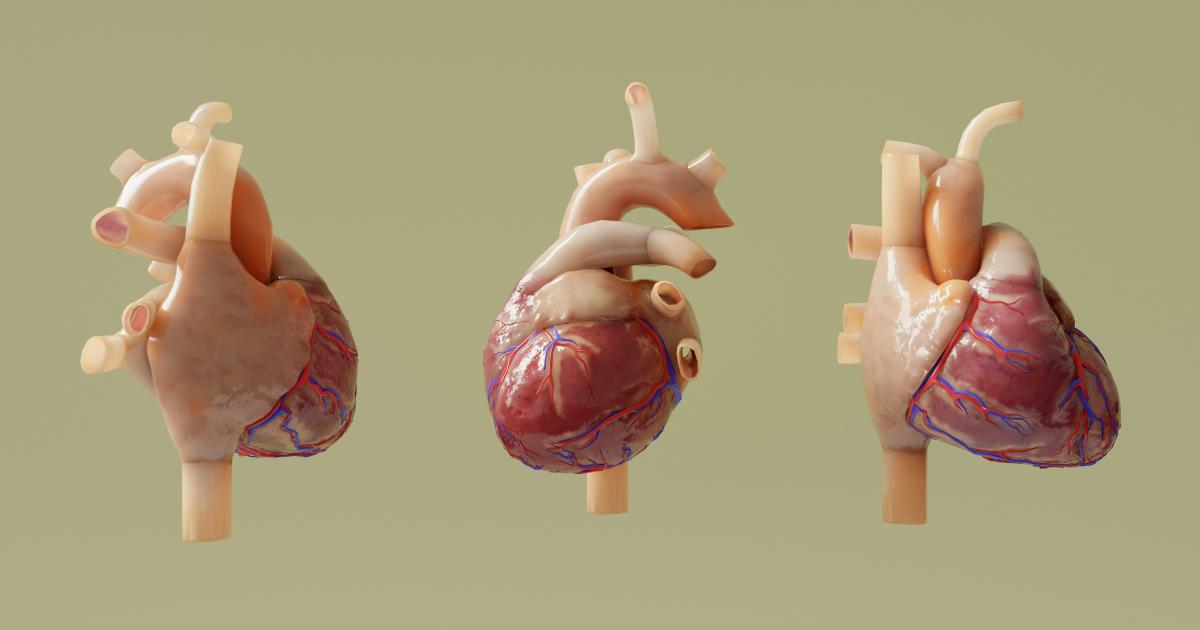

2. Healthcare and Life Sciences

In the healthcare and life sciences domains, interactive data visualizations play a crucial role in understanding patient outcomes, tracking disease patterns, and optimizing treatment strategies. By visualizing complex medical data, researchers and healthcare professionals can identify risk factors, monitor ongoing trends, and make more informed decisions to improve patient care.